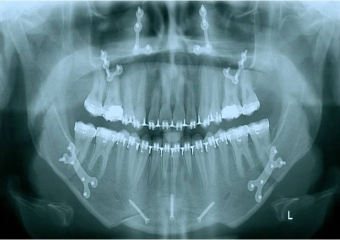

Raio x inicial